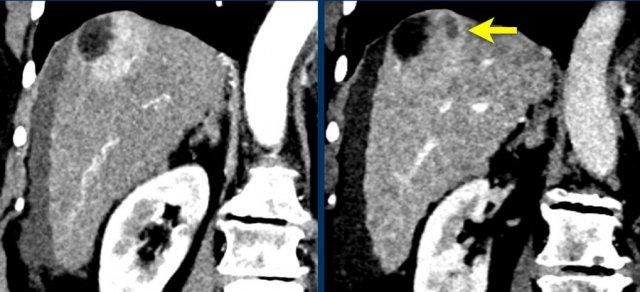

TRÁI: Tổn thương tăng ngấm thuốc phát hiện tại phân thùy 5. PHẢI: Theo dõi sau 3 tháng cho thấy tổn thương tăng kích thước.

Kích thước – Tăng trưởng vượt ngưỡng

Kích thước cũng là yếu tố quyết định tổn thương được xếp vào phân loại nào.

Tổn thương càng lớn, khả năng là HCC càng cao.

Tổn thương cần được đo trong thì, chuỗi xung hoặc mặt phẳng mà bờ tổn thương hiện rõ nhất.

Nên tránh đo kích thước trên thì động mạch và chuỗi xung DWI vì kích thước có thể bị ước tính quá mức do hiện tượng tổng hợp ngấm thuốc quanh tổn thương và biến dạng giải phẫu tương ứng.

Tăng trưởng vượt ngưỡng cũng là một dấu hiệu quan trọng.

Được định nghĩa là tăng kích thước hơn 50% trong vòng dưới 6 tháng.

Các hình ảnh cho thấy một tổn thương tại phân thùy 5 của gan có biểu hiện tăng ngấm thuốc thì động mạch.

Tổn thương đã tăng kích thước từ 8 mm lên 21 mm trong 3 tháng, đáp ứng tiêu chí tăng trưởng vượt ngưỡng.